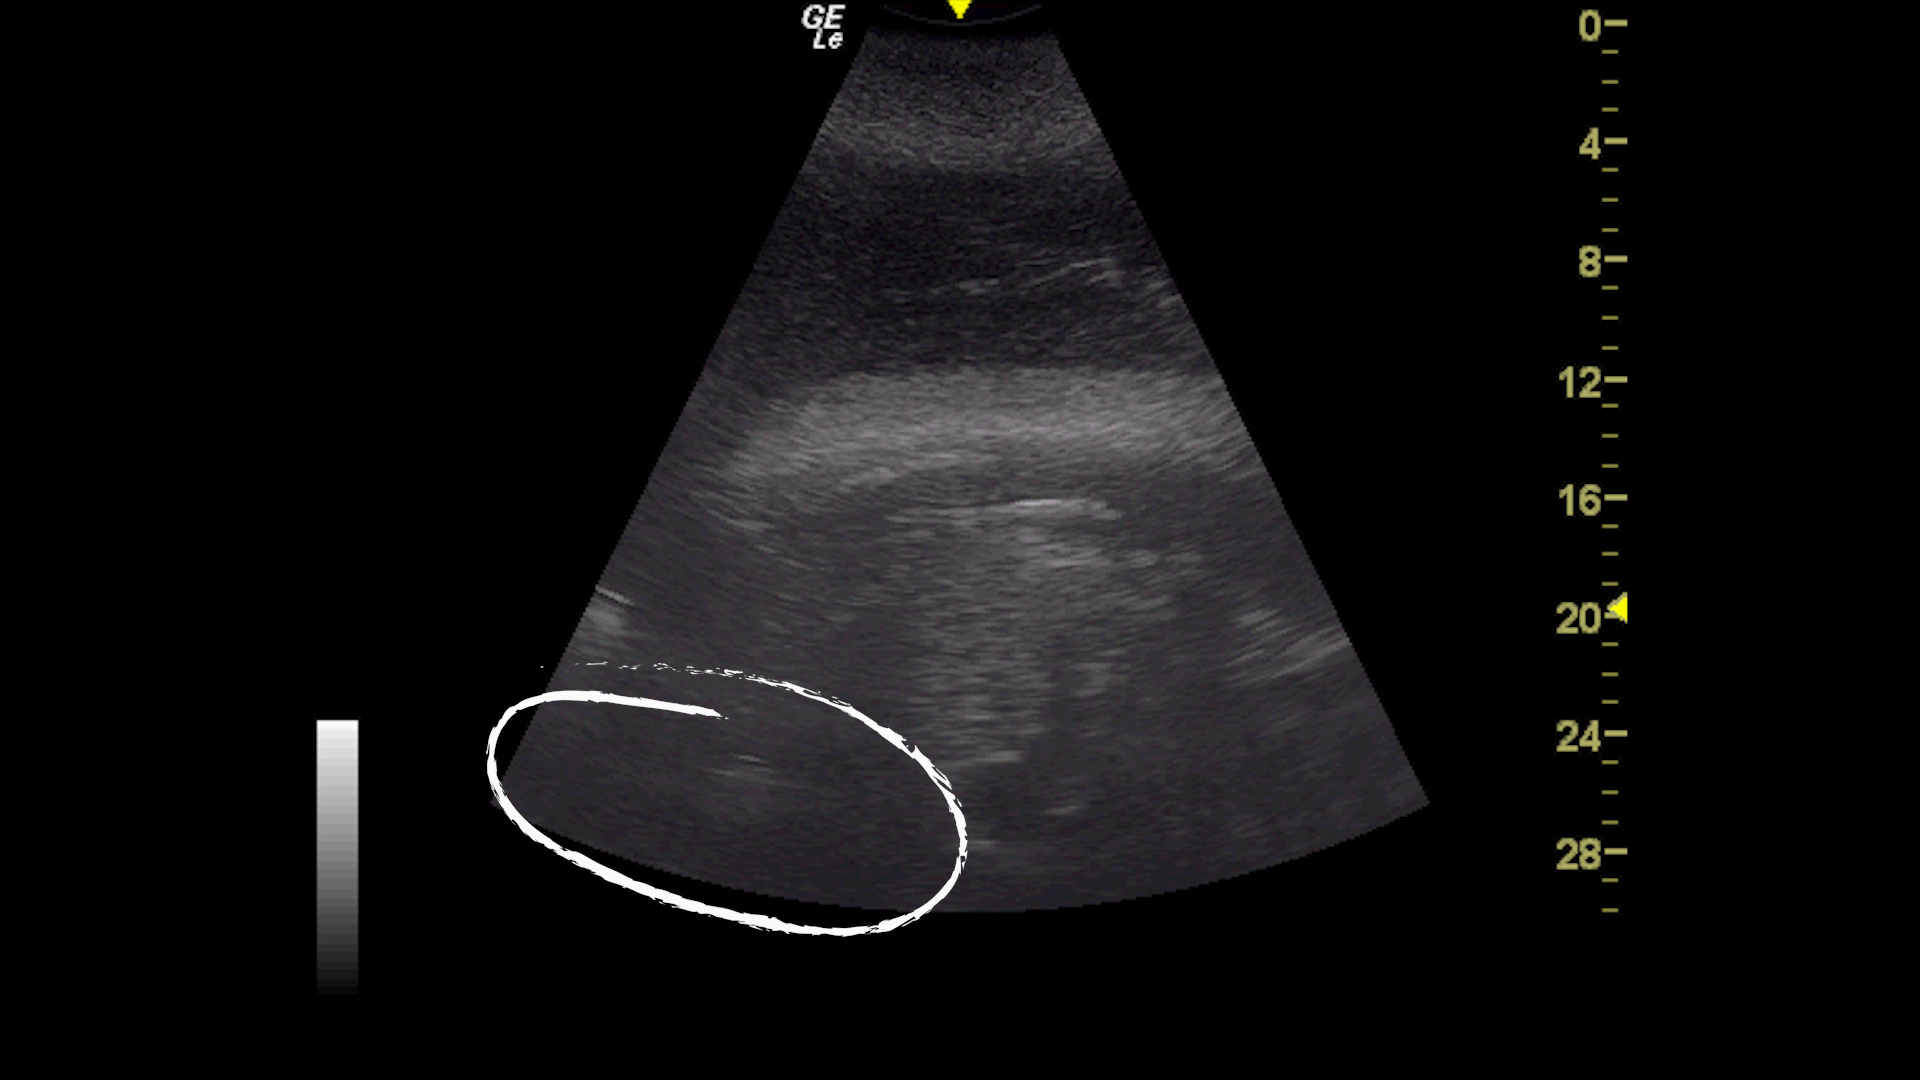

The care and standard medical training routines of Loro Parque’s orcas have been intensified with Morgan during the months of gestation, which has allowed for an exhaustive monitoring of the foetus and continuous observation of its evolution. “We do ultrasounds almost twice a week with a high frequency system that has no effect on the foetus and causes no discomfort,” explained Dr. Almunia.

These ultrasounds have allowed veterinarians to see that the foetus is very well positioned, that its heart is beating, and that everything is going as expected, so the Parque staff is now getting prepared to know when the exact time of birth will arrive. “And we are also getting everything organised so that, in the event that anything goes wrong, we can have everything ready to intervene on the spot,” said the Fundación’s Director. This is particularly relevant because, in the wild, 50 per cent of orca calves die before their first birthday, and, apart from that, one must take in consideration the handicap of Morgan’s deafness.